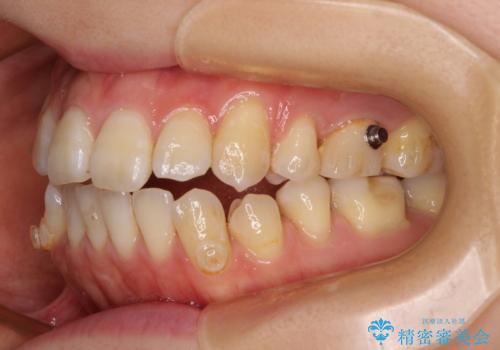

- 咬み合わない前歯と八重歯などのデコボコを気にして来院された患者様です。

上下前歯の位置を比較すると上顎が前方にあり、デコボコ改善でより上顎が前方に行く可能性があります。

開咬の改善にはインビザラインが有効であり、インビザライン単体での治療を検討しましたが、上顎前突を回避するために上顎左側第一小臼歯抜歯を行うこととしたため、補助装置とワイヤー矯正を併用した上で、インビザラインによる矯正治療を行うこととしました。